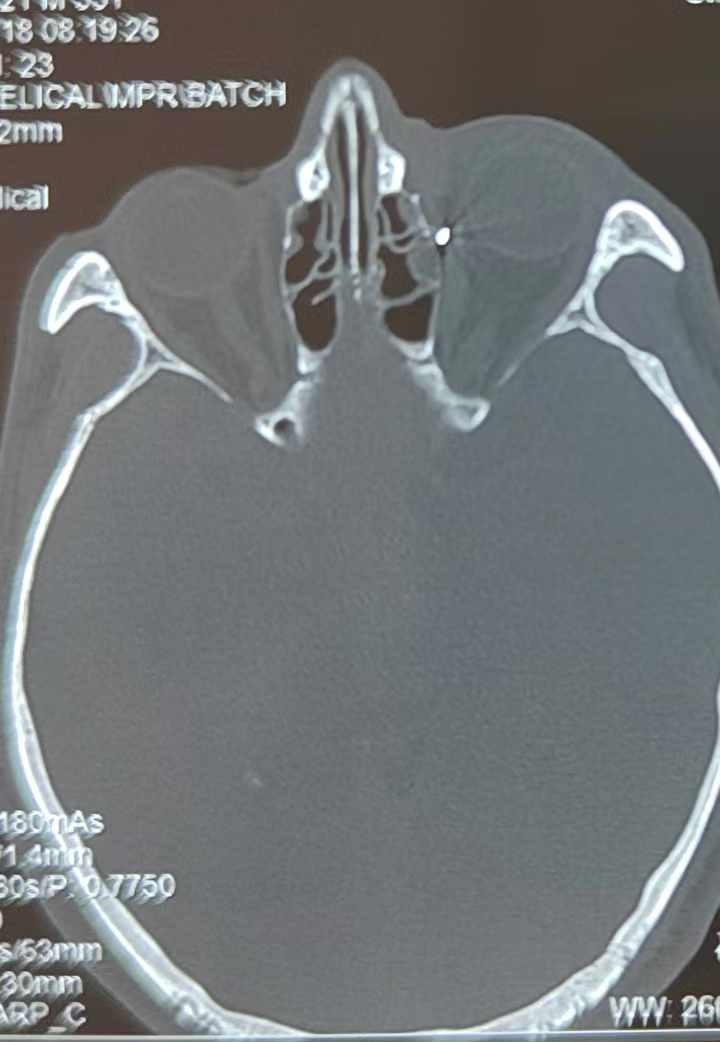

裝修工人高先生在作業(yè)過程中不慎被砸傷左眼,送至廈門眼科中心救治時(shí),眼外傷及眼底病2科副主任醫(yī)師李海波博士在CT檢查報(bào)告中發(fā)現(xiàn),進(jìn)入眼內(nèi)的異物在眶尖極為隱匿的位置,想要“不動(dòng)聲色”地取出來,有些難度。

從CT報(bào)告中可以看出,高先生眼內(nèi)的異物不是很大,但位于眼窩深處,緊鄰鼻骨,從CT影像判斷應(yīng)該是金屬或合金異物。一般臨床上遇到這樣的情況,醫(yī)生會(huì)建議“保守觀察”,若異物傷及神經(jīng)、發(fā)生炎癥感染等,則需到條件較好、有眼眶病和眼外傷專業(yè)醫(yī)師的醫(yī)院進(jìn)行二期眶內(nèi)異物取出術(shù)(2021年《中國眼眶異物診斷和治療專家共識》)。

李海波博士介紹,眶內(nèi)異物想要通過手術(shù)取出,難度很大,一是因?yàn)槲恢秒[匿,無法實(shí)現(xiàn)可視化操作;二是如果是磁性異物,現(xiàn)有手術(shù)工具磁性強(qiáng)度有限,很難吸出這么深的異物;三是可操作空間極為狹小,眶周軟組織多,異物周邊包裹緊密,像高先生這種情況,異物周邊還有很多神經(jīng)、血管,手術(shù)難度更高。

手術(shù)十分順利,李海波博士設(shè)計(jì)好了取出路徑,用這根細(xì)磁棒取出了一個(gè)米粒大小的鐵屑,過程中未造成二次傷害和大創(chuàng)面?zhèn)?。術(shù)后CT檢查顯示,高先生眼內(nèi)再無異物,他此時(shí)才松了一口氣。